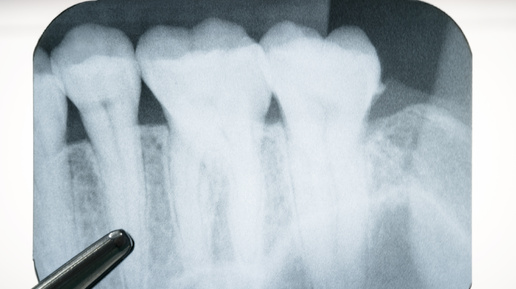

Кажется, что если нерв из зуба удалили, то и болеть в нем нечему. Но нервные волокна остаются в тканях, окружающих зуб. Именно от них могут исходить болевые сигналы. Разбираемся, почему такое бывает. Это нормальная реакция на лечение зуба. После удаления пульпы, или нерва зуба, врач специальным образом обрабатывает каналы и пломбирует их. В ответ на «ковыряние» инструментами в связках, окружающих зуб, развивается воспалительный процесс. Это приводит к появлению слабых ноющих болей. В норме воспаление затихает в течение 5—7 дней, и боли сами по себе проходят...

Представьте: вы приходите к стоматологу с острой зубной болью, врач диагностирует пульпит, тщательно очищает каналы, удаляет воспалённый нерв и ставит пломбу. Кажется, что проблема решена, но вдруг… спустя несколько часов зуб продолжает ныть. На следующий день неприятные ощущения не исчезают, а в некоторых случаях даже усиливаются. Возникает тревожный вопрос: "Почему болит зуб после удаления нерва? Это нормально или что-то пошло не так?" После эндодонтического лечения дискомфорт в зубе – не редкость...